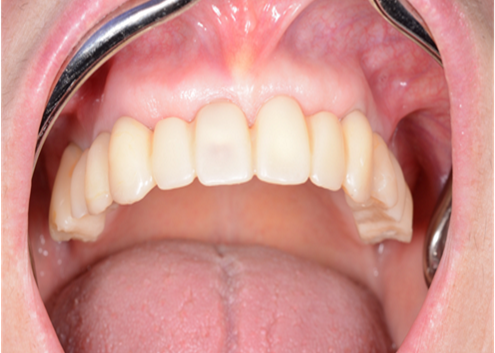

“AnyRidge shows excellent esthetic results

with Zirconia prosthesis in full-mouth rehabilitation case . ”

Clinical case: A Full transition from natural teeth to all-on-6 bridges

with AnyRidge implants

- Courtesy of Dr. Rabih Abi Nader, UAE -